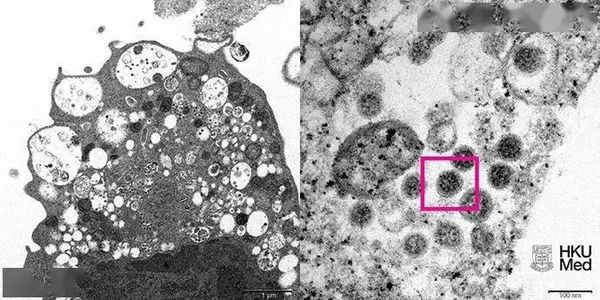

▎11月29日,香港大学微生物学系袁国勇研究团队成功从临床标本中分离出新冠病毒奥密克戎变异株。据袁介绍,获得奥密克戎的毒株,是研发针对该变异株灭活疫苗的第一步,目前香港大学已与内地数家疫苗公司分享成果,协助新冠疫苗的后续研发